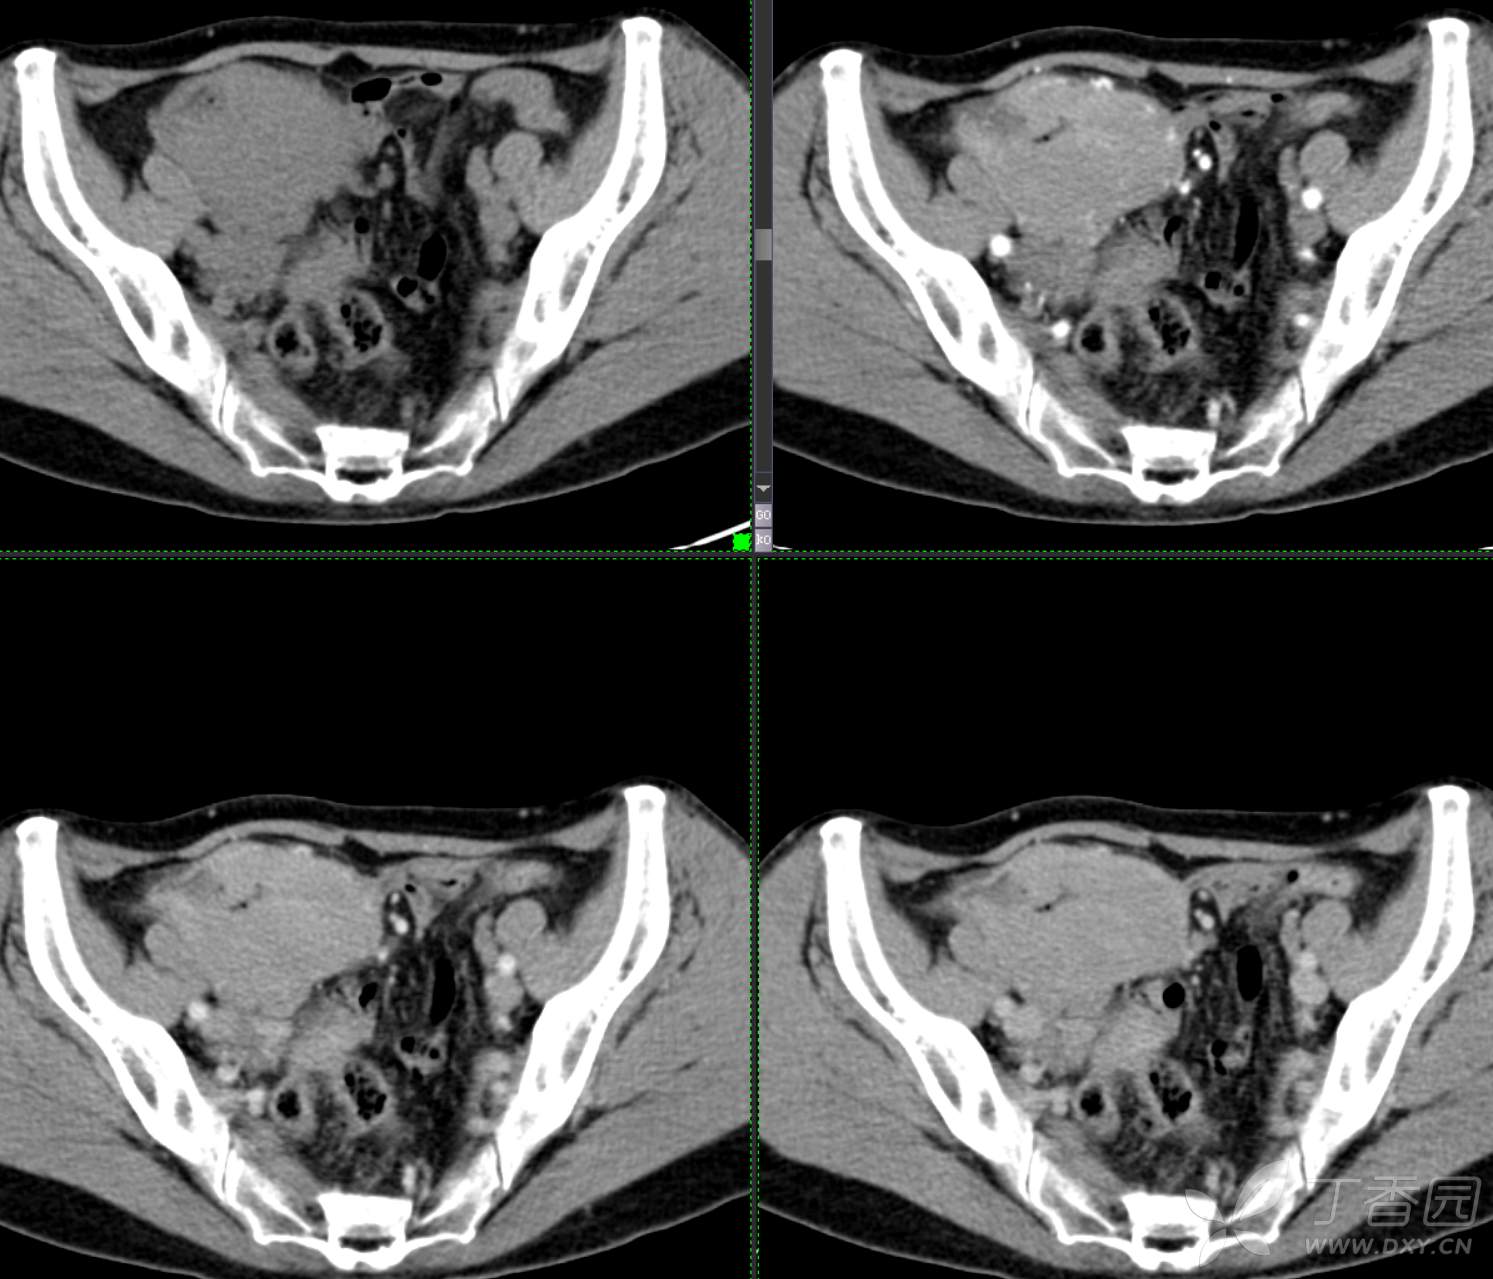

腹组13:患者,女,62岁,大便习惯改变2月余

主 诉: 【大便性状改变2月余】

现病史: 患者2月余前无明显诱因下出现大便次数增多,无明显血便黑便及粘液脓血便,大便次数由1次/日增加至2-3次/日,大便形状变细如小指,偶稀软不成形,无腹痛腹胀腹泻,无恶心呕吐、胸闷气促,肛门排气通畅,无发热盗汗。至当地医院就诊,行肠镜检查发现"回盲部占位"。为进一步治疗,我院门诊拟"回盲部肿瘤"收住入院。